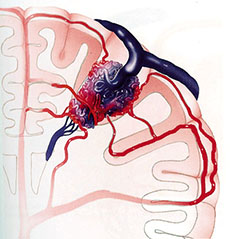

严重颅脑损伤、多发伤、复合伤

疾病介绍:严重颅脑损伤、多发伤、复合伤,多为交通、工矿事故、自然灾害、爆炸、火器伤、坠落、跌倒以及各种锐气、钝器对人体伤害。除正确诊断和及早手术外,加…【详细】